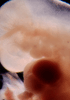

Carnegie Stage 14 (32 post-ovulatory days)

Most embryos at stage 14 are approximately 32 postovulatory days old and measure 5-7 mm in length. Distinguishing criteria for this stage include an open lens pit with invagination of the lens disc and elongated and tapering upper limb buds. The otic vesicle with a well-defined endolymphatic appendage is also a hallmark of this stage.

Photographs